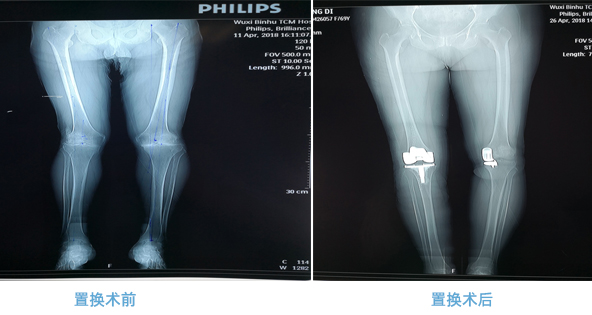

全膝人工关节置换术(total knee arthroplasty,TKA)是目前治疗膝关节退行性关节炎的常规治疗手段。术后可有效缓解膝关节疼痛、矫正畸形、改善膝关节的运动功能,被认为是目前治疗膝关节骨性关节炎最有效的方法。

我院骨伤科关节置换手术案例术前术后对比图